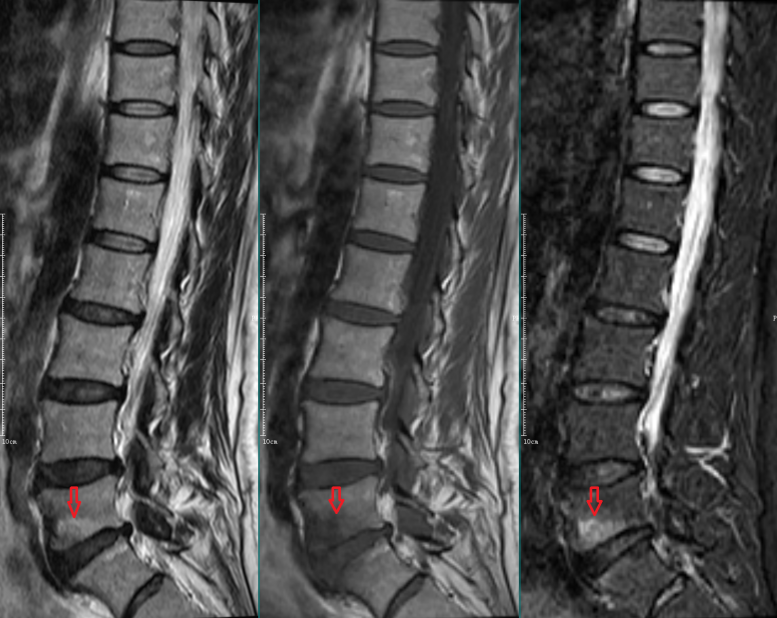

Modic Ⅲ型:

L5-S1椎间盘上下缘见条带状异常信号,T1WI、T2WI及STIR序列均呈低信号。